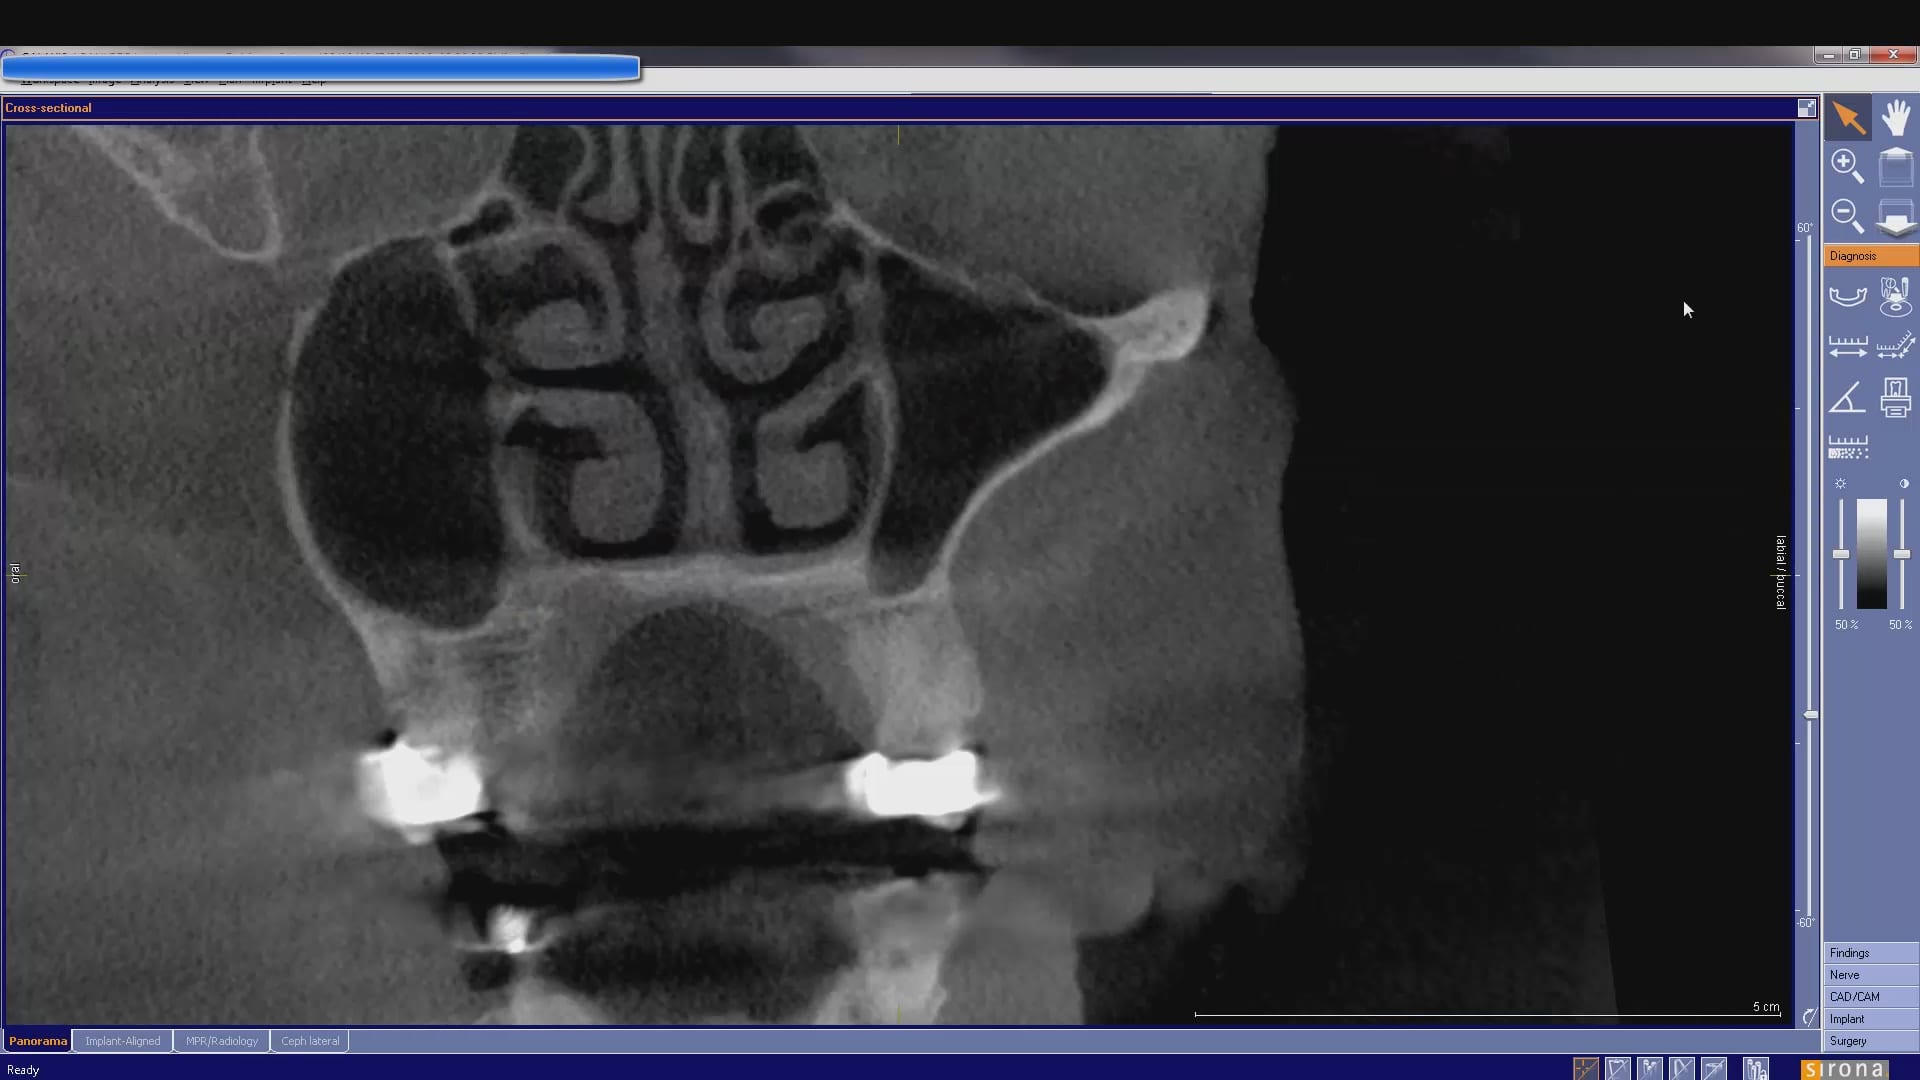

In this case presentation, we utilize the medit i500 to image the pre-existing crown and to fabricate a restoration that is a replica of the pre-existing condition. The patient was advised that the recurrent decay was in close proximity to the canal space and that endodontic treatment may be a possibility. The CBCT showed no evidence of any peri-apical radiolucency and the premolar tested vital prior to treatment